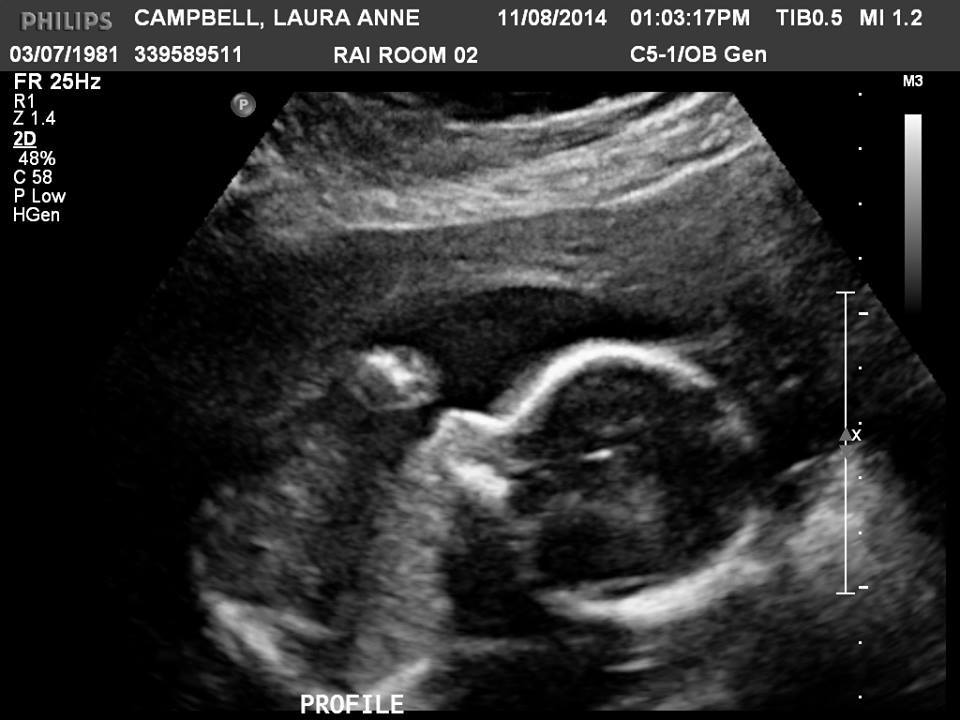

Want to take a guess? - skull theory - 20 week scan

What do you think it is?

Attachment 20343

girl

Looks girly